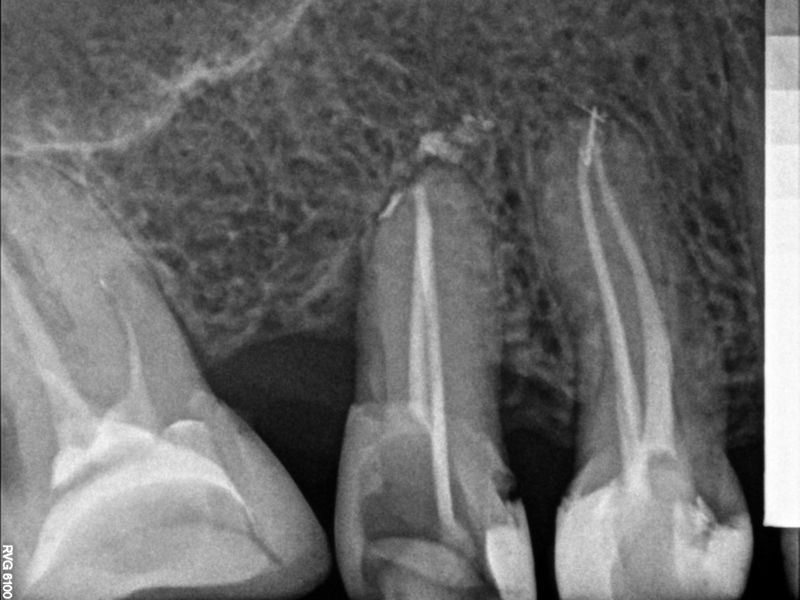

Bogata w płytki i leukocyty fibryna jest stosowana w regeneracji tkanek od ponad 15 lat. Pozytywny wpływ PRF (platelet-rich fibrin) na regenerację tkanek miękkich jest niewątpliwy, bezsporny i częściowo udowodniony w badaniach klinicznych i analizach biochemicznych. Wpływ PRF na regenerację tkanki kostnej jest obserwowany klinicznie, ale nadal niedostatecznie poznany jest mechanizm tego zjawiska.

Platelet- and leukocyte-rich-fibrin has been used in regeneration of tissue for more than 15 years. The positive influence of PRF on the regeneration of soft tissue is undoubtedly, without question and partially proven in clinical studies and biochemical analysis. Influence of PRF on regeneration of bone tissue is observed clinically but the mechanism of this phenomenon is still not sufficiently known.